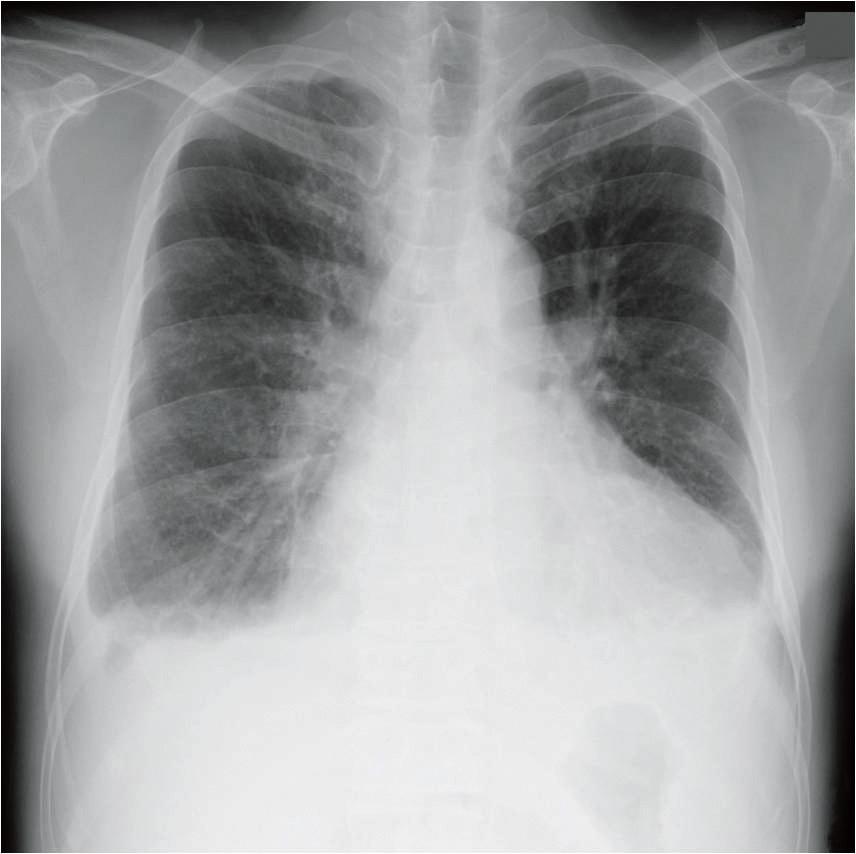

現症:意識は清明。身長167cm、体重64kg。体温36.1℃。脈拍124/分、不整。血圧146/84mmHg。呼吸数30/分。甲状腺の腫大を認めない。聴診上、V音を聴取する。両側の胸部でcoarse cracklesを聴取する。両側の下腿に浮腫を認める。 検査所見:心電図で心房細動を認める。胸部エックス線写真を示す。

37 この患者の胸部エックス線写真の所見として認められるのはどれか。

主訴は労作時呼吸苦。既往に未治療の高血圧とAfあり。現症で、頻脈、不整脈、V音、corse crackles。文句なしのうっ血性心不全。ここまで来れば答えは自明。37は、レントゲン見なくても、dが正解とわかる。38も当然aが正解。